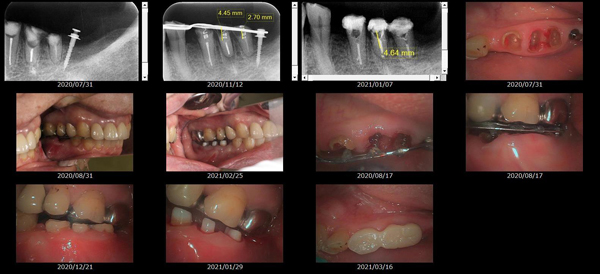

救歯MTM

虫歯が大きくて残せない歯、転倒などの事故により歯が根の深いとこで折れてしまったなどで、抜かざるを得ない歯を、骨の中に埋まっている健全な根を、骨の上に矯正的に引き上げることで、その歯を抜かず温存、救歯できる可能性のある治療方法です。

この特別な診療である救歯MTMは、以下のような特徴があります。

①健全な歯を、歯肉から見える位置にまで引き上げることで

根の治療の成功率を上げることが出来る。唾液には沢山の細菌がいます。唾液が入らない環境での根の治療を(神経の治療)を行うことで神経の治療、根の治療の成功率は格段と上がります。

②骨の上にある歯と土台で支える被せもの製作できる。

被せものを土台だけに頼ることなく、引き上げた健全な歯でも支えることで、歯への被せ物がしっかりと装着できるようになる。

③抜かずに歯を活かすことで、隣の歯を削るブリッジやインプラントにしないで済むことがある。

歯を矯正的に引き上げることで、その歯を救歯できるだけでなく、隣の歯を削るなどの侵襲を回避できる場合がある。

リスク

- > 歯を矯正的に引き上げることで、骨の中の根の長さは短くなりますが、その短さでも安定するという診断をした場合のみ施術になります。 残せる歯、根の長さが短い場合は、この救歯MTMの治療対象とならない場合がございます。

- > 治療期間が数か月~1年に及ぶ場合がある。

- > 費用が自費診療 44,000円 ~ 66,000円

- > 救歯MTMは救歯BTAセラミックと併用治療が必要な場合があります。

症例